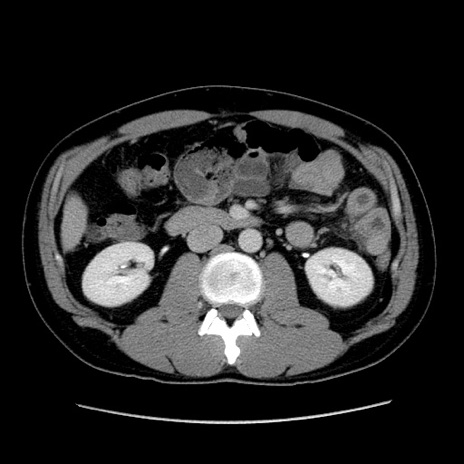

症例4(横断像)

【症例】30歳代男性

【主訴】腹痛、嘔吐

【現病歴】昨晩から突然の腹痛あり、その後嘔吐、軟便も出現。腹痛が改善しないため救急搬送となる。2日前にしめ鯖の食事歴あり。

【身体所見】意識清明、苦悶様、BP 135/90mmHg、BT 35.7℃、腹部:平坦、やや硬、心窩部〜臍部に自発痛、圧痛あり、筋性防御+、反跳痛-

【データ】WBC 8100、CRP 0.57